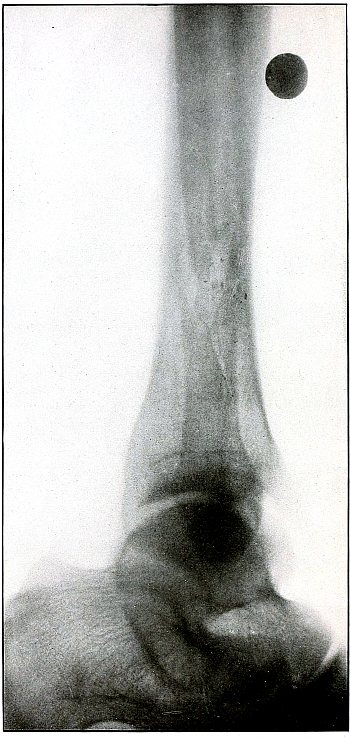

Rifle—Plate 59.

LOWER EXTREMITY.

Gunshot Wound of the Left Knee-Joint,

with Lodgment of the Missile in the Joint.

The course of the bullet was transverse, entering the capsule posterior to the patella without injury to the bone.

As its shadow projection is almost circular, the bullet must be standing almost on its end pointing toward the plate with its long axis almost parallel to the line of projection.

As the fibular side of the leg lay next to the plate and as the only slightly enlarged shadow of the bullet indicates it to be near the plate, its position is in the joint near the fibular side.

As the bullet is undeformed and its penetrating power very slight, its velocity was that of extreme range.

The emergency treatment, is, of course, a simple antiseptic dressing with the leg held in the most comfortable position by muscular action.

The subsequent treatment is removal of the bullet when proper surgical conditions obtain. [Pg 130]